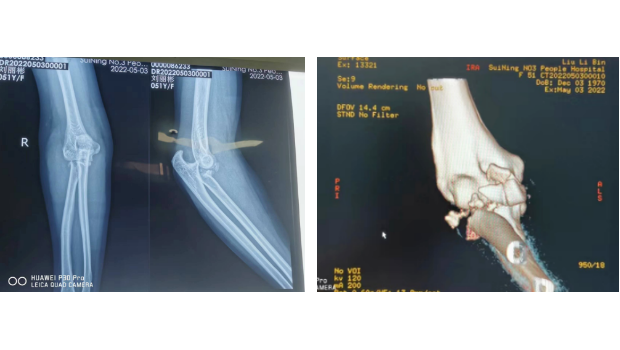

三管齐下!让“肘关节恐怖三联征”不再恐怖!

我院骨伤科为一位肘关节复杂骨折伴脱位患者成功实施了标准化手术,重建了一个“稳定、有力、活动良好”的肘关节。目前,该患者肘关节功能恢复良好,已康复出院。家住城南的...